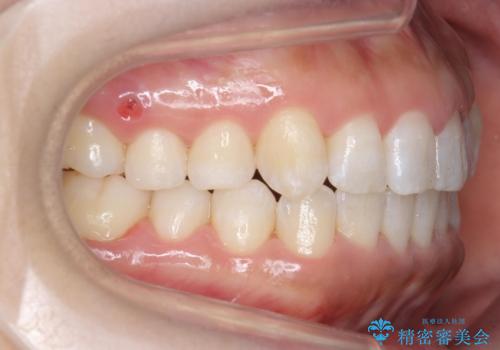

八重歯を非抜歯で マウスピースで治療 奥歯を後ろに下げてすき間を確保

- 八重歯を主訴に来院。

仕事柄ワイヤーが見えるよりはマウスピースで目立たなく歯並びを良くしていきたいとのことでした。

奥歯を後ろに下げてすき間を確保し、八重歯を引っ込めて並べる治療を行いました。

奥歯を後ろに下げるために、矯正用のミニスクリューを使用しています。

かなり真面目に使っていただいた印象で、綺麗に動きました。